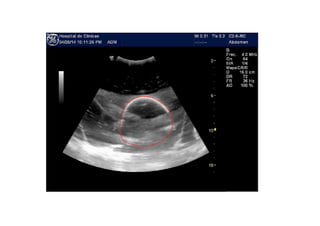

THE PROBLEM •Kidneys with polyquistosis are difficult to measure • Renal volume is needed for follow up • CT scan cannot be repeated How can renal volume be estimated non invasively?

• 6.

NEFROVOL Parallel 2Dimages along main axis User to define boundaries in each 2D Build a mesh Extrapolate at the ends Count contained elements Use scale to estimate volume